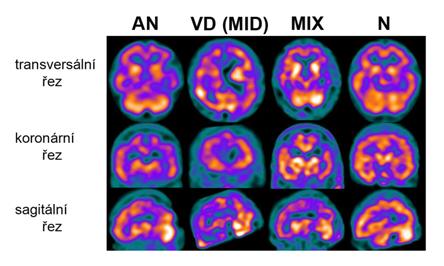

Na rozdíl od MR mozku poskytuje SPECT vyšetření mozku nový pohled na mozek. Zachycuje prokrvení a s ní související funkci dané části mozku, což se převádí do barevných map. Tak je možné sledovat oblasti mozku s dobrým nebo horším prokrvením a metabolickou aktivitou. Před vyšetřením se podává Chlorigen k zabránění hromadění vyšetřovací látky ve štítné žláze a slinných žlázách. Není nutné být nalačno. Po 10-15 minutách setrvání v klidu se podává vyšetrovací látka do žíly. V následujících asi 20 minutách se vleže v „tunelu“ zaznamenávají obrazy prokrvení mozku. Podrobnější informace o tomto vyšetření najdete zde.

Ukázkové snímky SPECT mozku z naší činnosti s perfúzním vzorcem typickým pro Alzheimerovu nemoc jako AN, pro vaskulární demenci jako VD (MID), pro smíšenou demenci jako MIX a normálním nálezem (N). Bližší definice perfúzních vzorců je v textu.